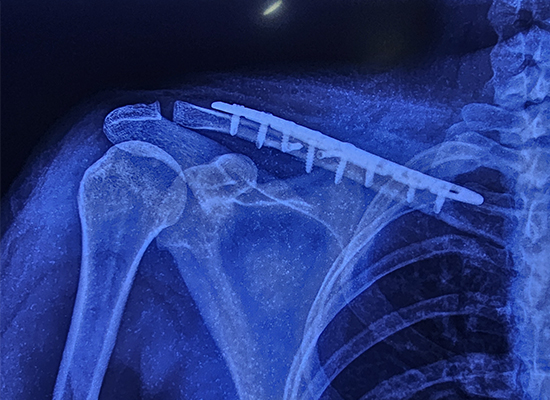

В ходе операции использовалась специализированная фиксирующая пластина S-ключицы — усовершенствованный имплантат, предназначенный для обеспечения стабильности при многофрагментарных переломах. Пластина с 8 отверстиями была выбрана из-за ее точного прилегания и способности поддерживать перелом в процессе заживления. Операция прошла гладко, никаких осложнений во время процедуры не возникло.

Тип имплантата: S-образная фиксирующая пластина ключицы.

Размер: 8 отверстий, правая сторона.

Материал: Титановый сплав для прочности и долговечности.

Применение: Предназначен для стабилизации переломов ключицы.

S-образный контур соответствует анатомии ключицы, равномерно распределяя нагрузку и предотвращая расшатывание или миграцию имплантата.